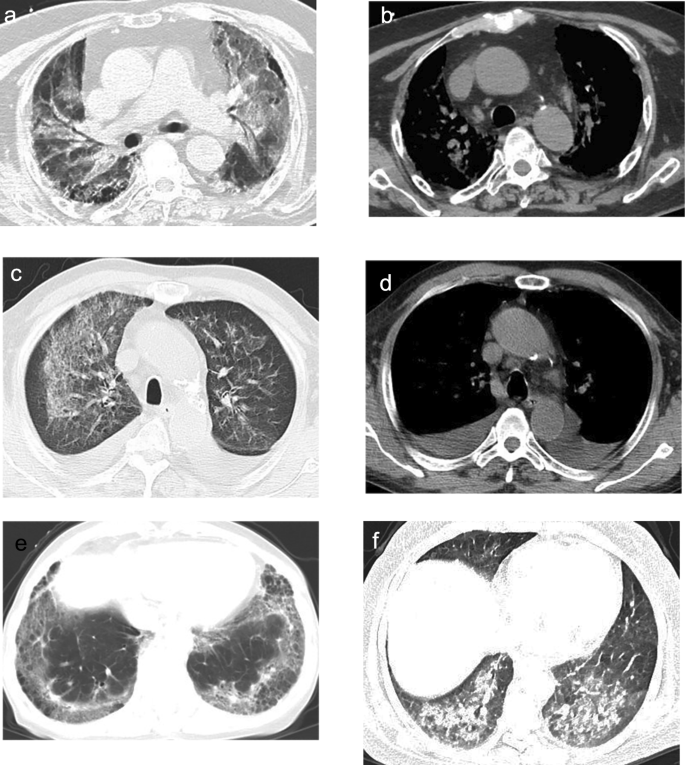

The inflammatory response (66.7% vs. 20.0%, P < 0.001) and perifissural consolidation (52.8% vs. 12.5%, P < 0.001) were more common in immunocompetent exudative PC. Immunocompromised exudative PC was more often with bilateral distribution (30.6% vs. 80.0%, P < 0.001), ground-glass reticular pattern (13.9% vs. 52.5%, P < 0.001), pleural effusion (0 vs. 22.5%, P = 0.007), and mediastinal lymphadenopathy (0 vs. 20.0%, P = 0.014). See Table 1; Figs. 2 and 3 for details.

CT findings of immunocompromised exudative PC. Axial CT images showed bilateral diffuse ground-glass opacities and consolidations (a) with mediastinal lymphadenopathy (b). Bilateral ground-glass reticular opacities (c), pleural effusions, and mediastinal lymphadenopathy (d) were displayed on axial CT. Axial CT image showed bilateral ground-glass reticular opacities with pleural-based involvement (e). Bilateral ground-glass opacities and consolidations were displayed on axial CT (f).